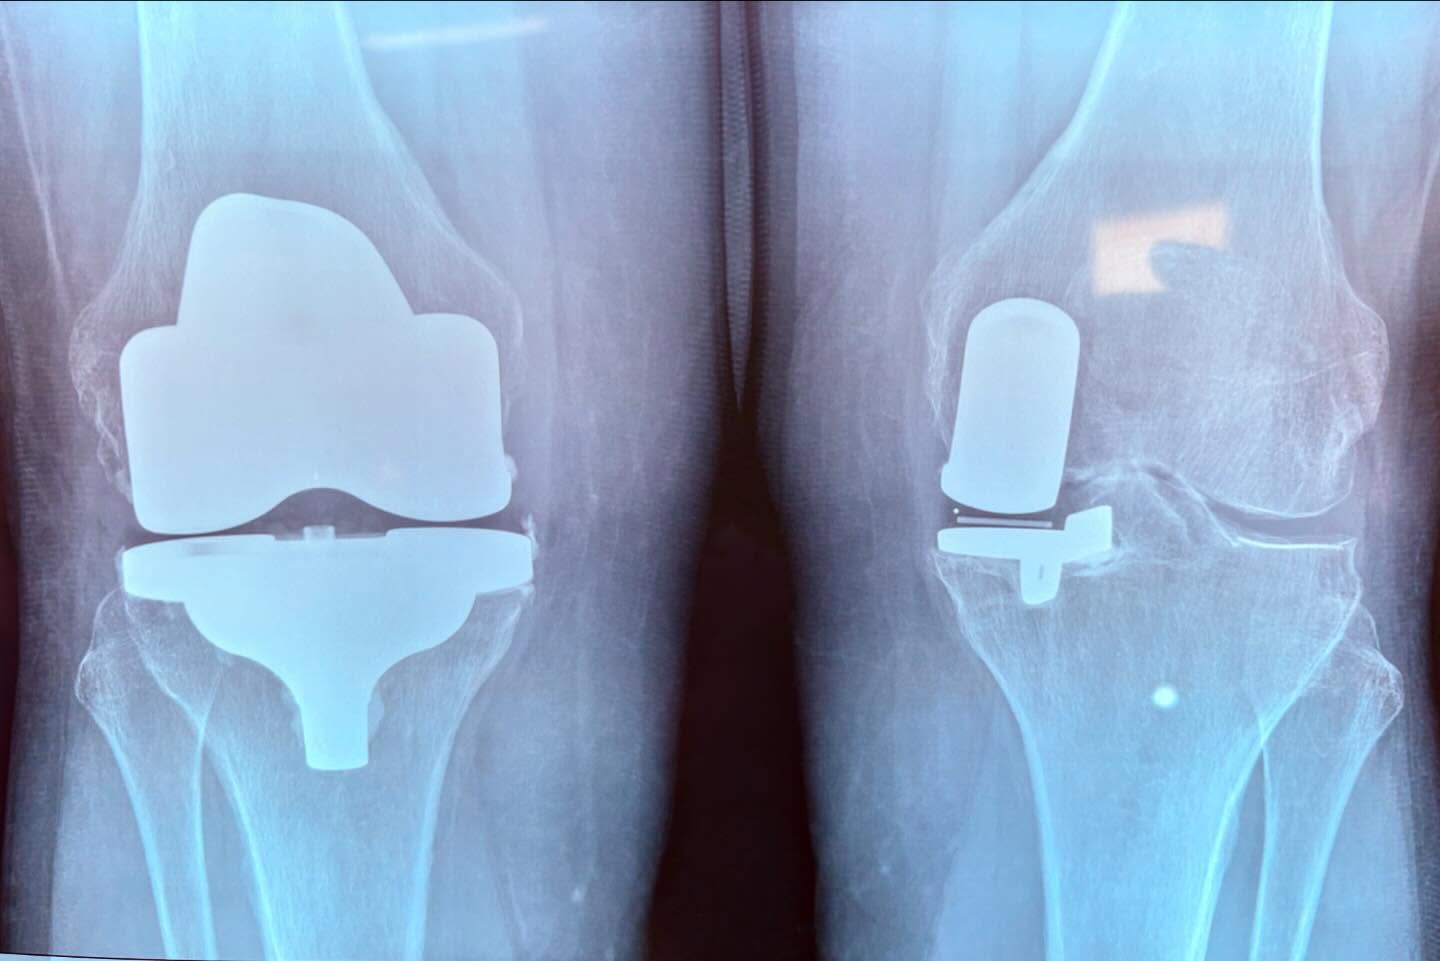

Ревизионное эндопротезирование на примере коленей пациента

При эндопротезировании не всегда удаётся сохранить часть сустава.Ревизионное эндопротезирование (т.е. повторное, производимое вторично с заменой изношенного имплантата на новый) почти всегда требует расширения зоны путём удаления части сустава, даже если при первой установке была лишь его частичная замена.На фото мы видим 2 колена одного пациента – ревизия левого коленного имплантата спустя 12 лет после частичного эндопротезирования + полная замена сустава на эндопротез (тотальное эндопротезирование).